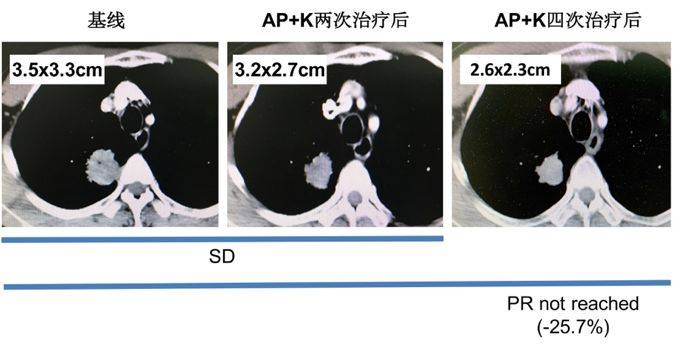

右肺上叶胸膜下软组织密度结节影,与胸膜关系紧密,最大截面积约3.5cm×3.3cm,考虑肿瘤性病变。

图2. 胸部增强CT(2019.01.18)

两次化疗+ pembrolizumab后,我们发现患者左侧颞叶、顶叶环形强化结节较前减小,周围水肿带范围较前减小。左侧海马区、右侧颞叶及额叶,强化结节较前明显减小,部分呈点状、部分显示不清。胸部CT提示肺部原发灶变化不明显。

继续这个治疗方案,于2019年4月10日至2019年5月14日对患者再行2次K药联合化疗治疗。再次行头颅增强核磁结果提示:左侧颞叶、顶叶强化结节较前减小,周围水肿带范围较前减小。原左侧海马区、右侧颞叶及额叶、右侧小脑半球强化结节未见明确显示。胸部CT结果提示右上肺结节较前减小(约25.7%),但未达到PR。

图5. 胸部增强CT(基线以及两次和四次联合治疗后)